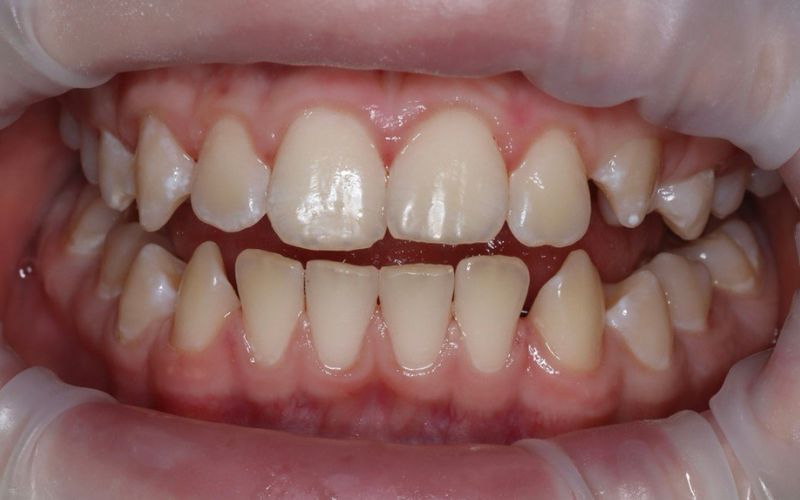

до

Пациентке 7 лет. Со слов мамы девочка не справляется с индивидуальной гигиеной полости рта. При осмотре было обнаружено большое количество налёта на зубах, который был визуализирован путём окрашивания.